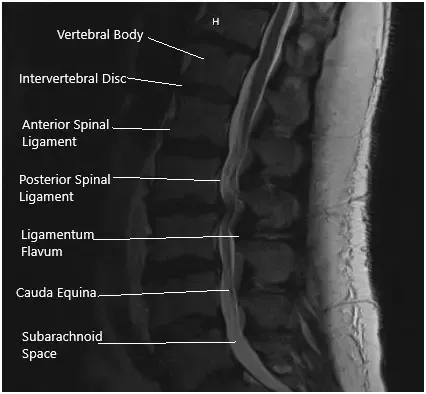

La resonancia magnética sugirió hipertrofia del ligamento flavico, contribuyendo a una estenosis espinal central grave en L2-L3. Hubo un estrechamiento leve a moderado del foramen neural izquierdo. Hubo un estrechamiento severo del foramen neural derecho con la eliminación de la raíz nerviosa L2 derecha saliente debido a una hernia discal lateral lejana.

En L3/4 había una protrusión discal y una hipertrofia de faceta y ligamento flavico, lo que contribuyó a una estenosis espinal central severa. Existe un estrechamiento leve a moderado de los forámenes neurales bilaterales.

Resonancia magnética de la columna lumbosacra en secciones sagital y axial.